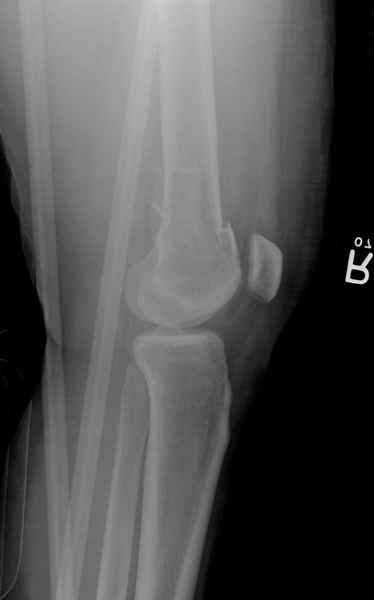

При наличии различных имплантов, любые варианты: слева (полу) открытым - мининвазивным, а справа закрытым интрамедуллярным методом, его считаем более чем приемлемым для фиксации данных переломов.

Проксимальная и дистальная блокировка, независимо от техники введения штифта, ретроградно или антеградно, гарантирует сращение сегментарных переломов бедра без укорочения. Штифты диаметром 12 мм с блокировкой сверху и вниз двумя шурупами выдерживают вес 75 кг больного, что позволяет раннюю профилактику контрактур.

Погоня за "красивой рентгенограммой" не всегда оправдана для фиксации кости, где имеется массивное мягкотканое покрытие. Если так уж хочется исправить положение кости, то при наличии ЭОП, большие костные фрагменты могут быть развернуты или приближены к основному фрагменту методом применения Joystick.

Из-за вариабельности установки дистальных шурупов и возможности перкутанного введения проксимально предпочитаем DePuy Polyax, хотя на сегодняшнем маркете множеств вариантов фиксации дистального бедра перкутанном методом.